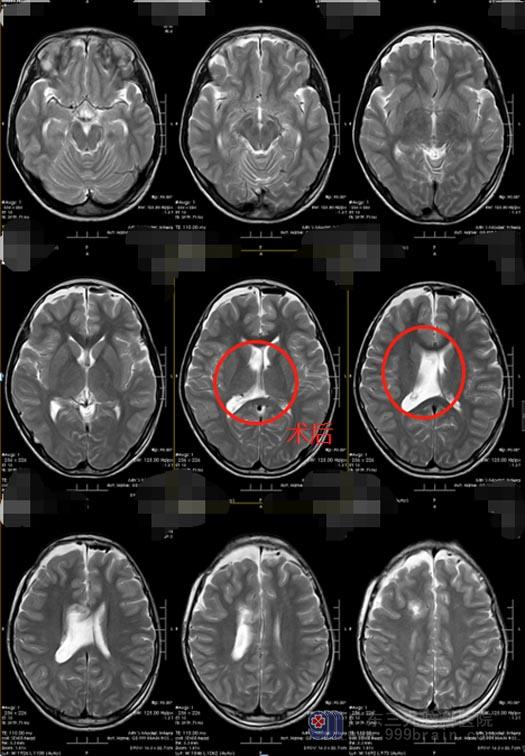

成成的手术指征明确,其囊肿充斥了整个右侧侧脑室,开颅手术易引起出血,创伤也较大,若没有完全切除,术后容易复发;选择内镜辅助下进行囊肿切除术,不但创伤小,并且效果也较好。在制定了严密的手术方案之后,成成顺利完成了“神经内镜辅助下右侧侧脑室病变切除术”,囊肿被完全切除。术后,成成恢复良好,头晕、头痛症状消失。